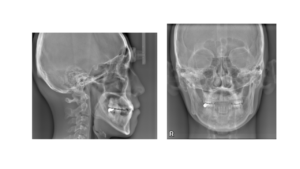

・レントゲン・顔貌写真: 歯の根っこの状態はもちろん、顎の関節の形を詳しく見ます。20代の頃に「顎がパキパキ鳴っていた」という経験はありませんか? それは、顎のクッション(関節円板)がズレ始めたサインです。

MRI検査のご提案:必要に応じて、専門施設でのMRI撮影をお勧めすることもあります。クッションが今どこにあるのかを正確に知ることで、根拠のある治療が可能になります。